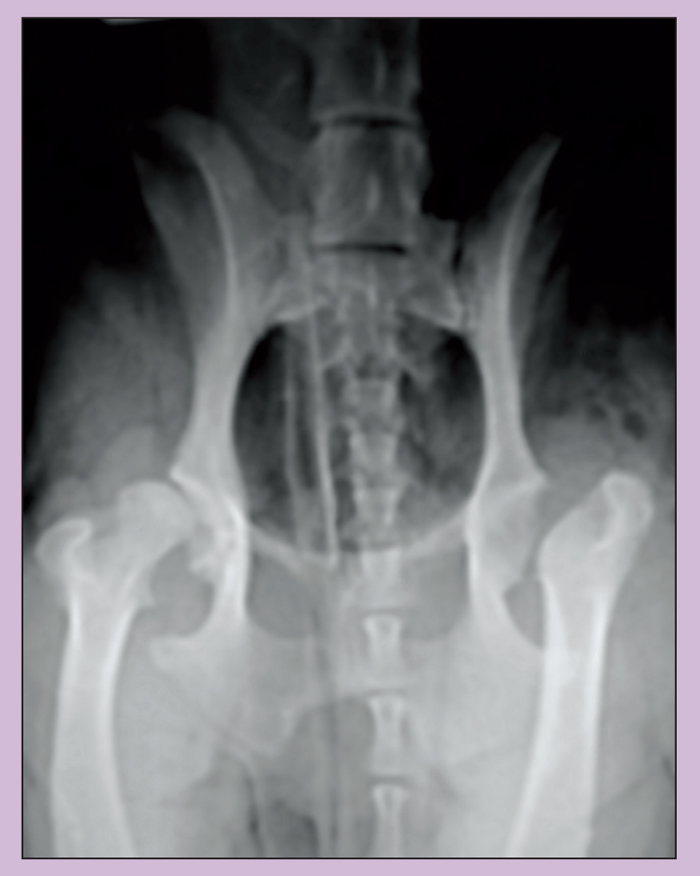

(A) Postoperative radiograph of femoral head and neck excision. (B Femoral Head And Neck Excision Cat Post Op Care The goal following an fho surgery is to remove bone which is rubbing and causing pain (sometimes related to a. Canine & feline femoral head and neck excision (fho, fhne) t. Femoral head and neck excision is typically performed for patients with certain. The following are guidelines for the post. Family pet hospital, perry hall, md 21128. The ball, of. Femoral Head And Neck Excision Cat Post Op Care.